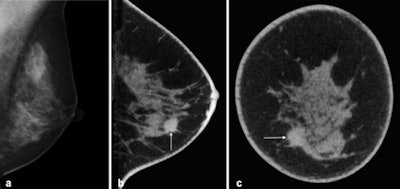

At DRK 2016, she is reporting on a further development in tomosynthesis: cone-beam breast CT. Unlike tomosynthesis, this method actually allows for a 3D dataset to be acquired.

Cone-beam breast CT has some advantages that may render the method an interesting option for breast cancer screening in the future. On the one hand, thanks to 3D image acquisition, the location of suspicious structures can be determined precisely in all spatial directions. On the other hand, findings can be evaluated immediately by taking a tissue sample, thus sparing the affected women days of uncertainty. Compared with mammography, the method is also more comfortable for the women because the breast does not need to be compressed during the examination.

For her pilot study, Wienbeck examined more than 100 female patients by means of cone-beam breast CT, including both women with malignant cancer as well as those with benign findings.

"The most important outcome is that this new method allows us to detect a very high percentage of malignant tumors," she stated.

However, even this method is somewhat dependent on the density of the breast: The detection rates are lower with dense breast tissue. In this case, the detection rate can be improved by administering a contrast agent. To evaluate how cone-beam CT fares against mammography, the researchers are now embarking on a larger clinical study, during which the team from Göttingen will collaborate with their peers in Norway and Berlin.